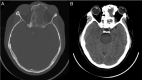

Juvenile psammomatoid ossifying fibroma (JPOF) is a rare, benign type of ossifying fibroma. JPOFs predominantly present as rapidly growing masses with a high recurrence rate. We report a 40-year-old male patient who suffered from a large tumor with multiple invasions into the paranasal sinuses. Total excision was performed, and significant relief of clinical symptoms was recorded after 4 months of follow-up. Multi-departmental management involving radiologists, neurology surgeons, craniofacial surgeons, pathologists, and otolaryngologists is vital for JPOF treatment. First-line treatment options include total or partial resection, depending on the patient's condition.